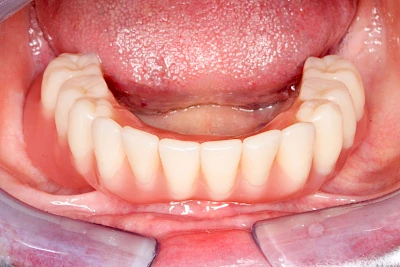

Implantate: Prothesen

Bei herausnehmbaren Prothesen werden Implantate eingesetzt, um den Halt und den Tragekomfort der Prothesen zu verbessern. Dazu kommen verschiedene Verbindungselemente zum Einsatz:

- Teleskope

- Kugelköpfe

- Tellerförmige Lokatoren

- Stege

- Magnete (selten)

Neben rein implantat-getragenen zahnärztlichen Versorgungen werden bei herausnehmbaren Prothesen Implantate auch in Sinne einer "strategischen Pfeilervermehrung" ergänzend zu eigenen Zähnen zur Verankerung eines Zahnersatzes genutzt.

Varianten zur Verankerung von abnehmbarem Zahnersatz auf Implantaten